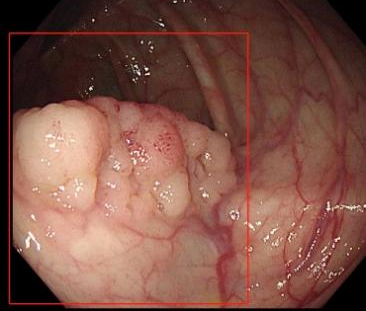

在肠镜检查时,医生看着屏幕,觉得“眼花缭乱”,密密麻麻的肠息肉有数百枚!

随后的病理结果提示,小秦确诊结直肠多发息肉病,其中多枚较大息肉已经进展为腺癌,且CT显示肝脏有异常结节,考虑癌细胞转移,已经到了晚期,仅切除肠道病变对生存意义不大。目前小秦在我院肿瘤科进行化疗,希望能将肿瘤缩小转化,创造手术机会。医护对此都感到很痛心。

(肠息肉—癌前病变—肿瘤)